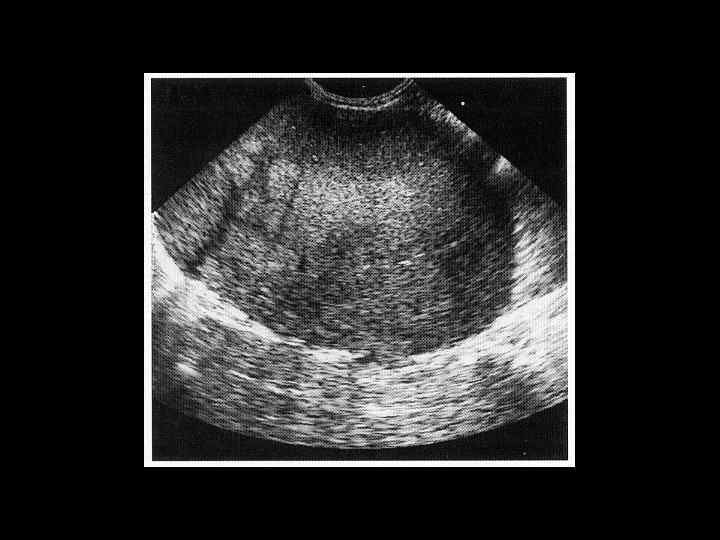

АКТУАЛЬНЫЕ ВОПРОСЫ РЕНТГЕНОЛОГИИ ЛУЧЕВАЯ ДИАГНОСТИКА ЗАБОЛЕВАНИЙ СЕЛЕЗЕНКИ Травма и инфаркт селезенки